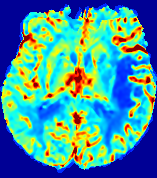

LesionRefer to captionRefer to captionRefer to captionRefer to captionRefer to captionRefer to caption𝐕rgbsubscript𝐕𝑟𝑔𝑏{\bf{V}}_{rgb}Refer to captionRefer to captionRefer to captionRefer to captionRefer to captionRefer to caption𝐕2subscriptnorm𝐕2{\|\bf{V}}\|_{2}Refer to captionRefer to captionRefer to captionRefer to captionRefer to captionRefer to captionRefer to caption3.53.53.52.82.82.82.12.12.11.41.41.40.70.70.70.00.00.0(mm/s)𝑚𝑚𝑠(mm/s)D𝐷DRefer to captionRefer to captionRefer to captionRefer to captionRefer to captionRefer to captionRefer to caption0.0200.0200.0200.0160.0160.0160.0120.0120.0120.0080.0080.0080.0040.0040.0040.0000.0000.000(mm2/s)𝑚superscript𝑚2𝑠(mm^{2}/s)Slice #1Slice #2Slice #3Slice #4Slice #5Slice #6

Figure 4: PIANO feature maps for another patient in the ISLES 2017 training set, where the lesion is located in the right hemisphere. Top row: segmented stroke lesion region (white) on different slices. The corresponding slices for the PIANO feature maps are shown in the following rows.

For a better insight into an estimated velocity field 𝐕𝐕{\bf{V}} and diffusion field 𝐃𝐃{\bf{D}}, we compute the following maps: (1) 𝐕rgbsubscript𝐕𝑟𝑔𝑏{\bf{V}}_{rgb}: Color-coded orientation map of 𝐕=(Vx,Vy,Vz)T𝐕superscriptsuperscript𝑉𝑥superscript𝑉𝑦superscript𝑉𝑧𝑇{\bf{V}}=(V^{x},V^{y},V^{z})^{T}, obtained by normalizing 𝐕𝐕{\bf{V}} to unit length and mapping its 3 components to red, green, blue respectively; (2) 𝐕2subscriptnorm𝐕2\|{\bf{V}}\|_{2}: 222 norm of 𝐕𝐕{\bf{V}}; (3) D𝐷D: scalar field in Eq. 5.

Fig. 3 and Fig. 4 show the PIANO feature maps estimated from two ISLES 2017 patients: all are highly consistent with the lesion in both cases. Details of the blood flow trajectories are revealed in 𝐕rgbsubscript𝐕𝑟𝑔𝑏{\bf{V}}_{rgb} by the ridged patterns and the sharp changes of colors in the unaffected (right) hemisphere, while the flat patterns appearing within the lesion provide little directional information about the velocity and indicate low velocity magnitudes. Velocity magnitudes are more directly visualized via 𝐕2subscriptnorm𝐕2\|{\bf{V}}\|_{2}, from which one can easily locate the lesion where 𝐕2subscriptnorm𝐕2\|{\bf{V}}\|_{2} is low. D𝐷D also indicates lower diffusion values in the lesion, though with less contrast potentially due to the fact that it captures the accumulated effect of CA diffusion at the voxel-level.